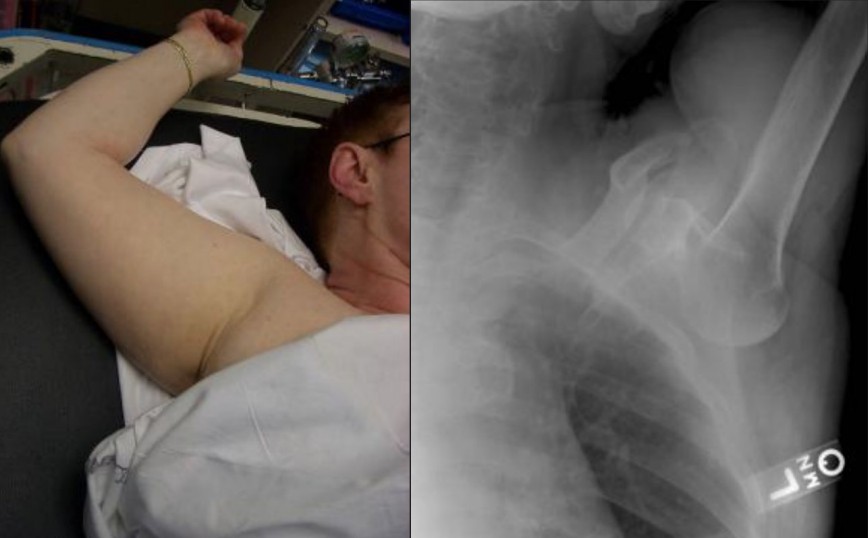

Shoulder dislocation

A 45-year-old man presents after a fall with an abnormal shoulder position. Clinical images and X-rays are provided.